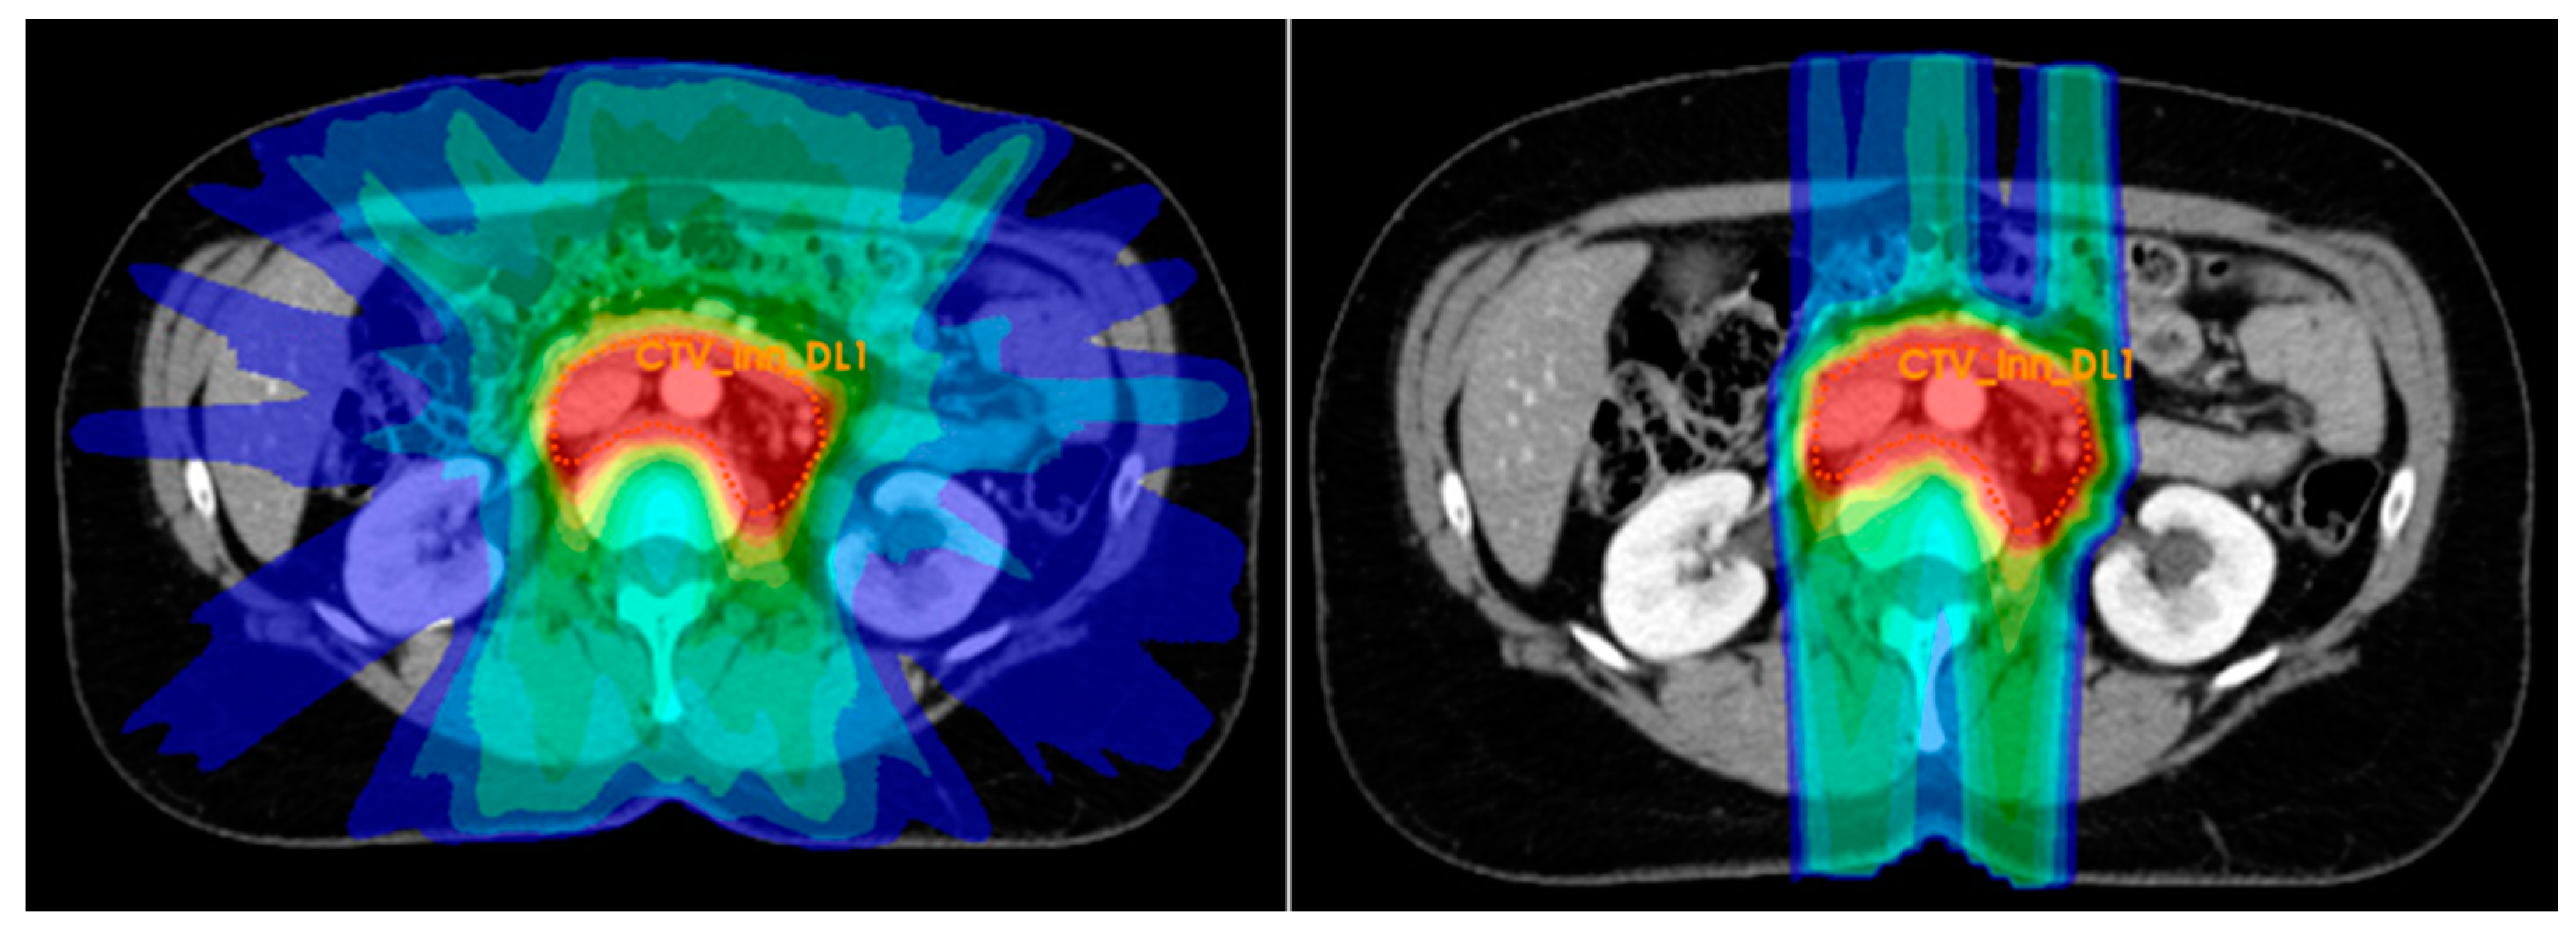

2.7.2. External Beam Radiation Therapy Planning

2.7.3. External Beam Radiation Therapy Delivery